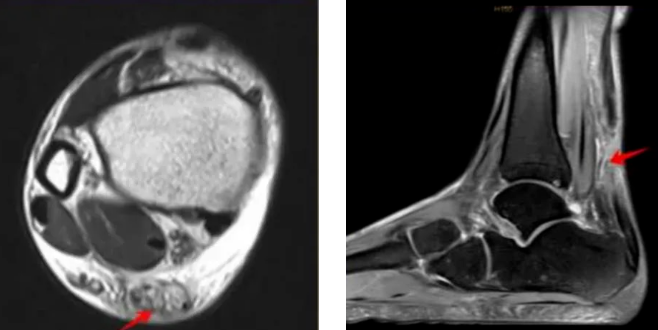

就医后,最常用明确诊断的影像学检查主要包括超声检查和MRI检查,对怀疑有跟腱止点撕脱骨折者,还需要完善X线、CT检查。